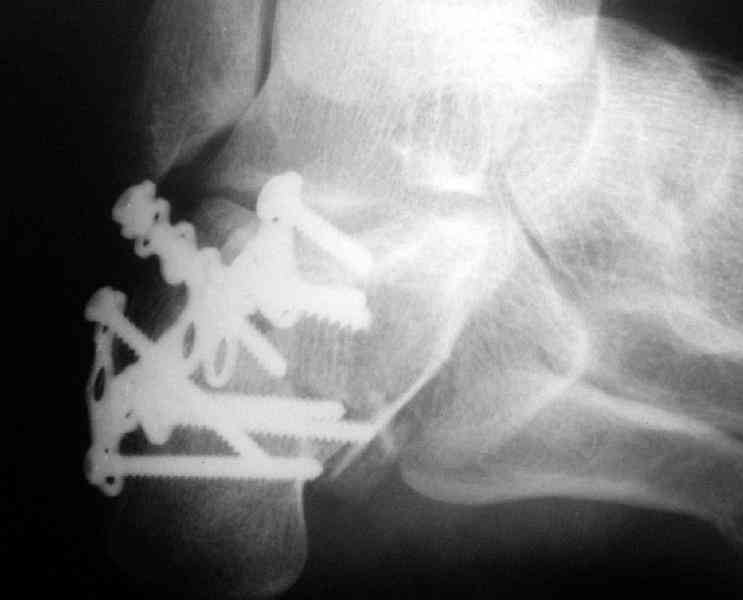

Пяточной пластиной

Открытый и закрытый способы лечения.

Its a comminuted one.

I would have a CT prior 2 surgery(If u have to postpone a surgery for it - I would operate without one)

I myself would reduce it with EX-FIX and depending on the result would consider a plate on the table.

MOST OF MY COLLEGUES WOULD OPEN IT LATERALLY( a flap) and having a proper reduction would put a plate.

Если нет опыта в остеосинтезе пяточной пластиной то лучше начать с экскохлеации полости кистозного образования и заполнения его остеоиндукторами Коллапан, Тутопласт, etc.Закрытая репозиция с рентгенконтролем на столе и перкутанная фиксация спицами пяточного бугра с фиксацией в эквинусе могут дать вполне приемлемый результат.

Вправление задней фасеты с восстановлением таранно-пяточного угла возможно минимально-инвазивным методом Essex-Lopresti - под ЭОП или графическим контролем введенной в пяточный бугор толстой спицей или стрежнем Штеймана, которые служат рычагом. Для удержания вводим несколько тонких спиц Киршнера, фиксация в эквинусе.Подробнее в Margo anterior 1-2 2000\издание АО Матис в России, на сайте www.mathys.ru в архиве есть все выпуски. Метод внедрен у нас с 2000 года и дает неплохие результаты.